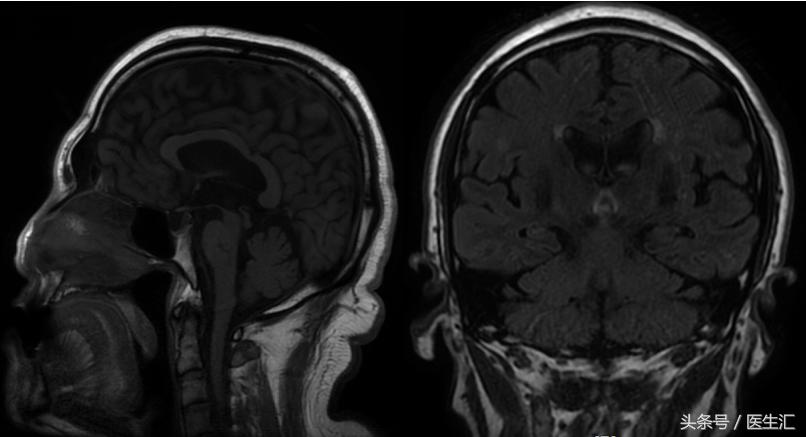

影像检查